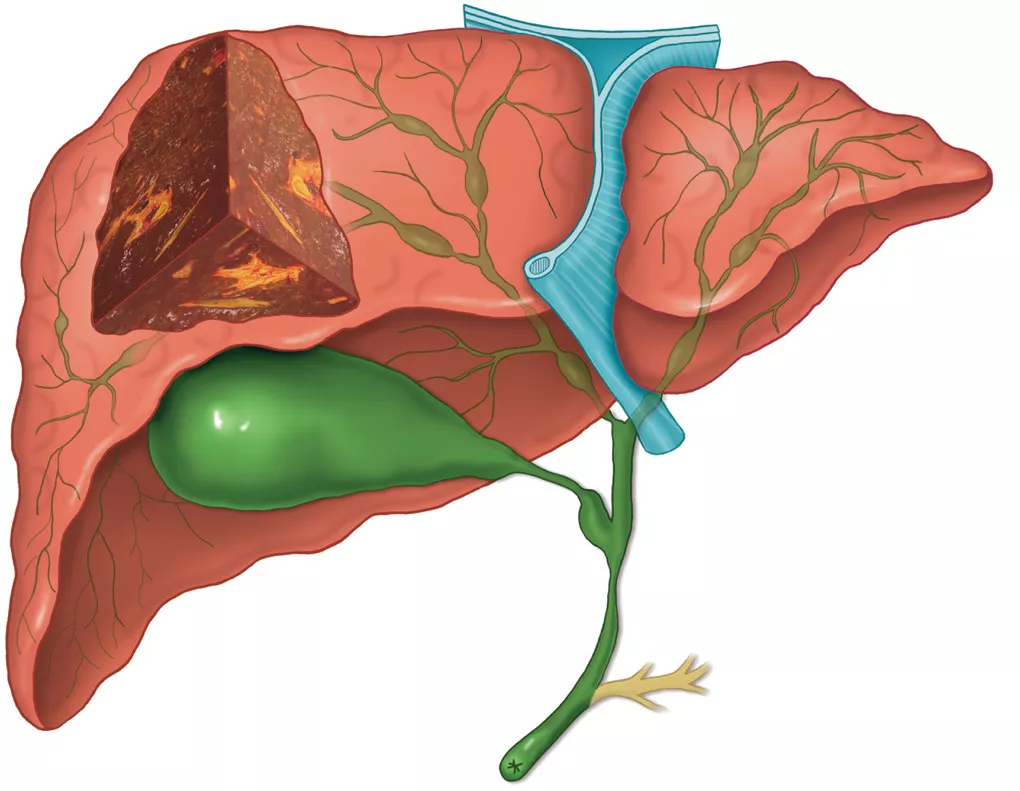

Рисунок 1. Патологические изменения желчевыводящих путей при первичном склерозирующем холангите (макроскопические изменения) [5].

Наблюдается множество стриктур с мешковидными расширениями как внутрипеченочных, так и внепеченочных желчных протоков, что являются типичной холангиографической картиной. Стриктуры приводят к регионарному холестазу, очаговому перибилиарному фиброзу и в конечном итоге к холестатическому циррозу печени. Изолированное внутрипеченочное поражение встречается у 30% пациентов, а изолированное внепеченочное поражение встречается редко. Почти у 90% пациентов наблюдается аномалии желчного пузыря, а камни в желчных протоках обнаруживаются у 25% пациентов.